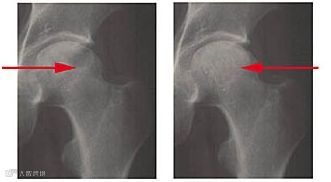

选择2010年5月至2013年5月在沈阳医学院附属中心医院骨外四科住院的股骨头坏死病例27例, 男21例, 女6例;年龄36~55岁, 平均40.5岁。致病原因:长期饮酒19例, 外伤后5例, 长期服用激素2例, 不明原因1例。提取培养人脐带MSCs。并对患者进行髓芯减压植骨术联合脐带MSCs移植治疗。27例患者术后12~20个月 (平均18个月) 随访, 按Harris髋关节功能评分, 疼痛消失, 能从事各种劳动, X线片或MRI显示股骨头基本正常23髋 (76.7%) ;疼痛明显减轻, 行走基本正常或者轻微跛行7髋 (23.3%) ;行走间距延长28髋 (93.3%) , 髋关节功能障碍明显好转18髋 (60%) 。

髓蕊减压术加脐带间充质干细胞移植治疗股骨头坏死,有效再造坏死区骨质。